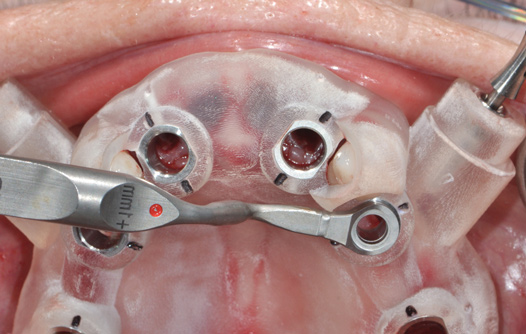

Fig 14. Printed static guide used to precisely control preparation of osteotomy (Fig 14) and delivery of the implant through the guide (Fig 15).

Figure 14

Fig 15. Printed static guide used to precisely control preparation of osteotomy (Fig 14) and delivery of the implant through the guide (Fig 15).

Figure 15